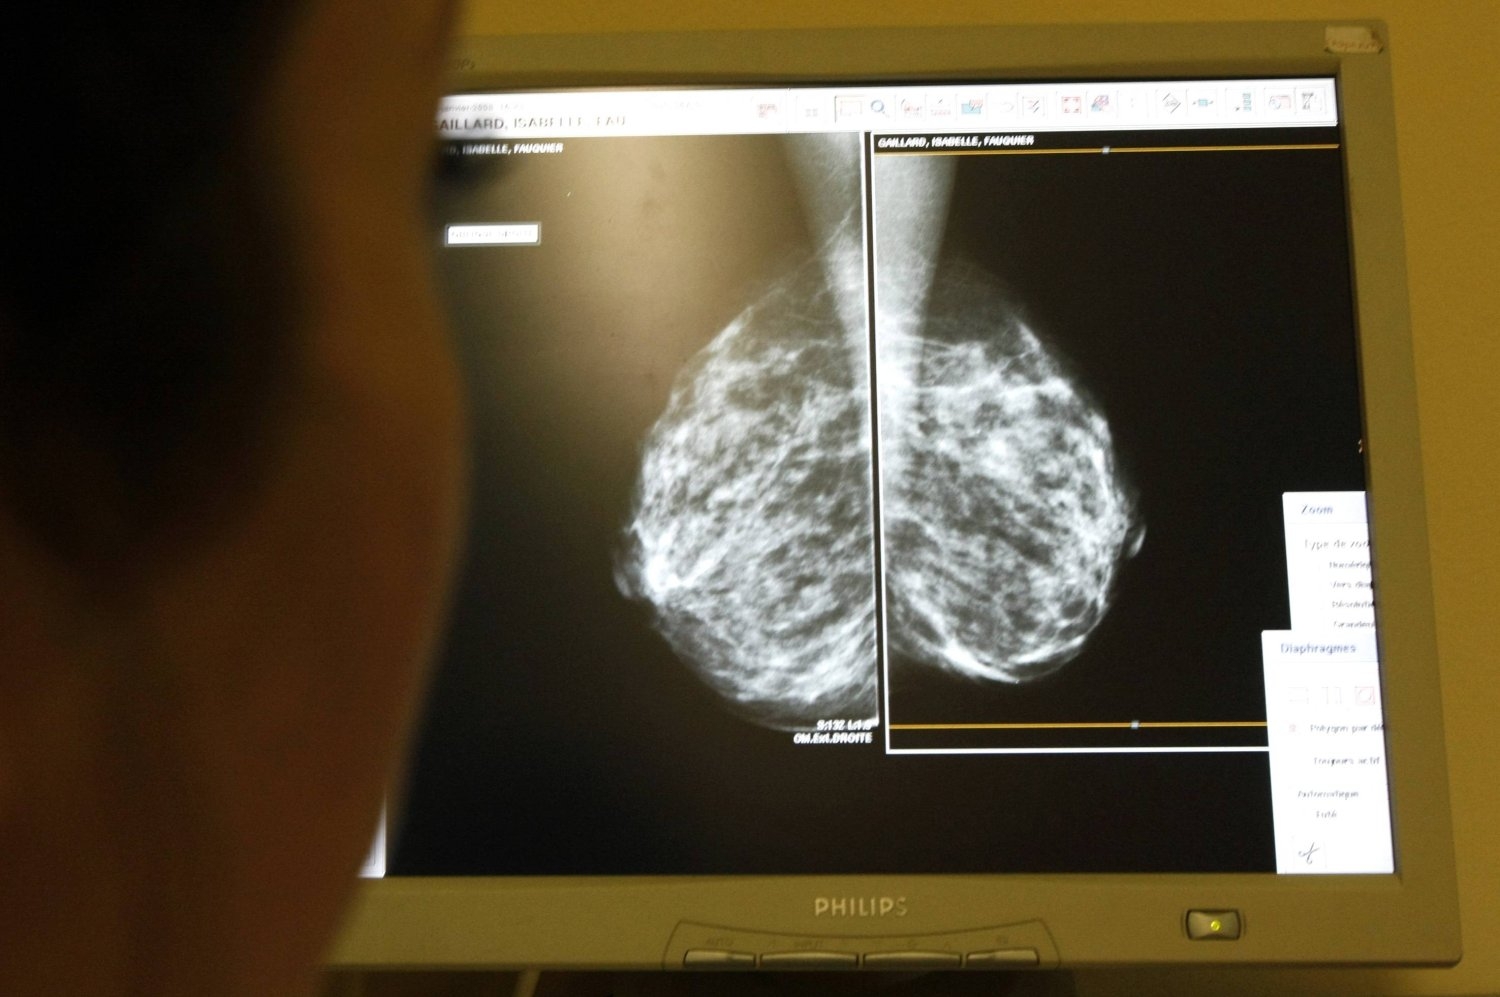

هل يصاب الرجال بسرطان الثدي؟

عندما يفكر الناس في سرطان الثدي، يفكر معظمهم في سرطان الثدي لدى النساء. لكن الحقيقة هي أن الرجال يصابون بسرطان الثدي أيضاً. ووفق تقرير نشرته شبكة «سي إن إن»، يشكل الرجال نحو 1 في المائة من جميع حالات سرطان الثدي، ما يعني أن 1 من كل 726 رجلاً سيتم تشخيصهم بسرطان الثدي في حياتهم. ويعدّ أحد أكبر التحديات المتعلقة بسرطان الثدي لدى الرجال هو أنه غالباً ما يمر دون أن يلاحظه أحد عموماً بسبب عدم وجود إرشادات فحص روتينية مثل تلك الخاصة بالنساء.

مقارنة سرطان الثدي عند الرجال والنساء

تتشابه سرطانات الثدي عند الرجال والنساء، ولكن هناك أيضاً بعض الاختلافات الرئيسية. نظراً لأن أنسجة الثدي عند الرجال أقل، فإن السرطان يكون غالباً أقرب إلى جدار الصدر، ما قد يؤثر على كيفية انتشاره. يبلغ معدل البقاء على قيد الحياة لمدة 5 سنوات للرجال المصابين بسرطان الثدي نحو 77.6 في المائة، مقارنة بـ86.4 في المائة عند النساء، ويرجع ذلك جزئياً إلى التشخيص المتأخر. ومع ذلك، فإن العلاجات (الجراحة والإشعاع والعلاج الكيميائي) هي نفسها إلى حد كبير بالنسبة للرجال والنساء.